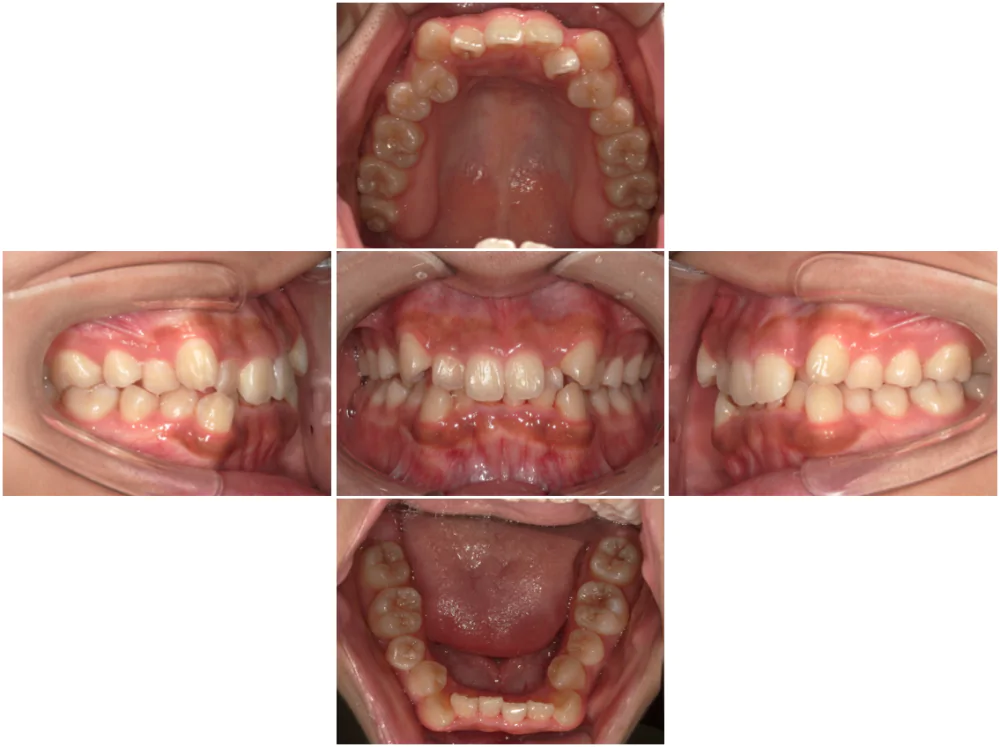

症例2

| 来院時の主訴 | 前歯がガタガタ |

| 医院での対応や適用装置 | マウスピース矯正装置を使用して主訴である叢生の改善を行ないま |

| 通院期間 | 1年3ヶ月 |

| 通院回数 | 9回 |

| 治療費用総額 | 819,500円(税込) |

| リスクと副作用 | 矯正治療による歯の移動に伴う痛み、歯根吸収、虫歯 |